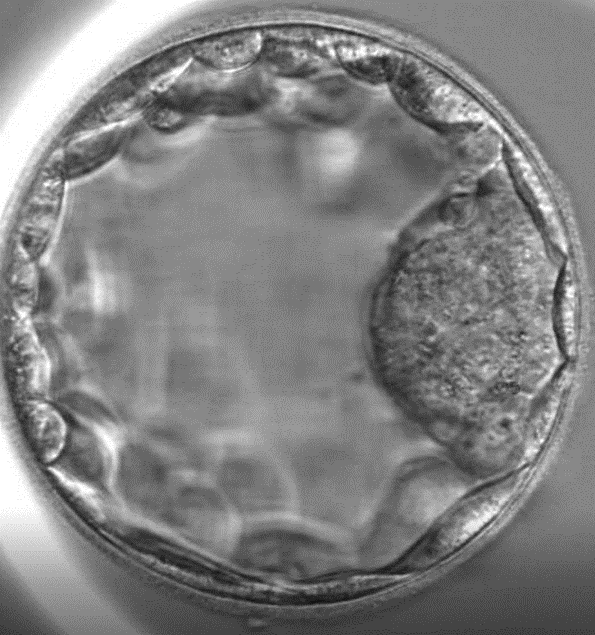

Donating my eggs in my 30s